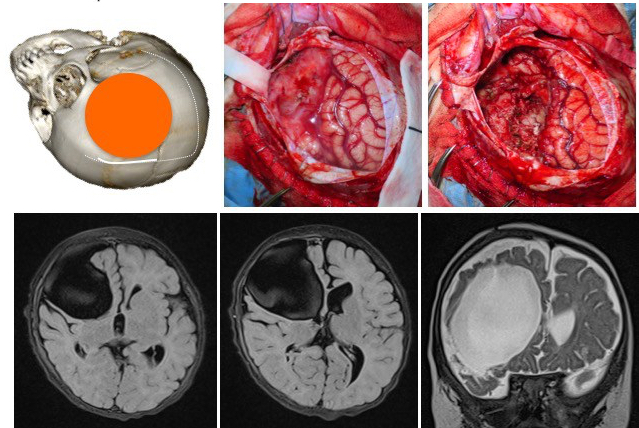

macroscopiquement, la tumeur a le plus souvent une attache méningée, et elle est d’emblée apparente à l’ouverture durale. elle est de consistance ferme, avec un fort contingent kystique ; elle se clive relativement bien des structures cérébrales et vasculaires adjacentes. lors des récidives cependant, elle peut adhérer intimement aux vaisseaux du polygone de willis et infiltrer le cortex et les ventricules.